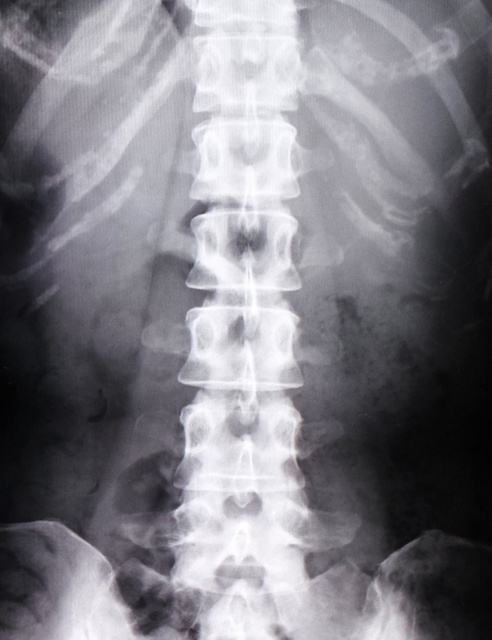

また、腰椎椎間板ヘルニアなどの脊椎の不調でいわゆるぎっくり腰が起こることがありますが、その痛みが起こるのが腰というより背中であることもあり、その場合ぎっくり背中と呼ばれることもあります。

脊椎が原因になる場合はそこから出ている神経が刺激を受けることで、その神経の支配領域に痛みの他しびれや感覚異常などの症状を起こします。